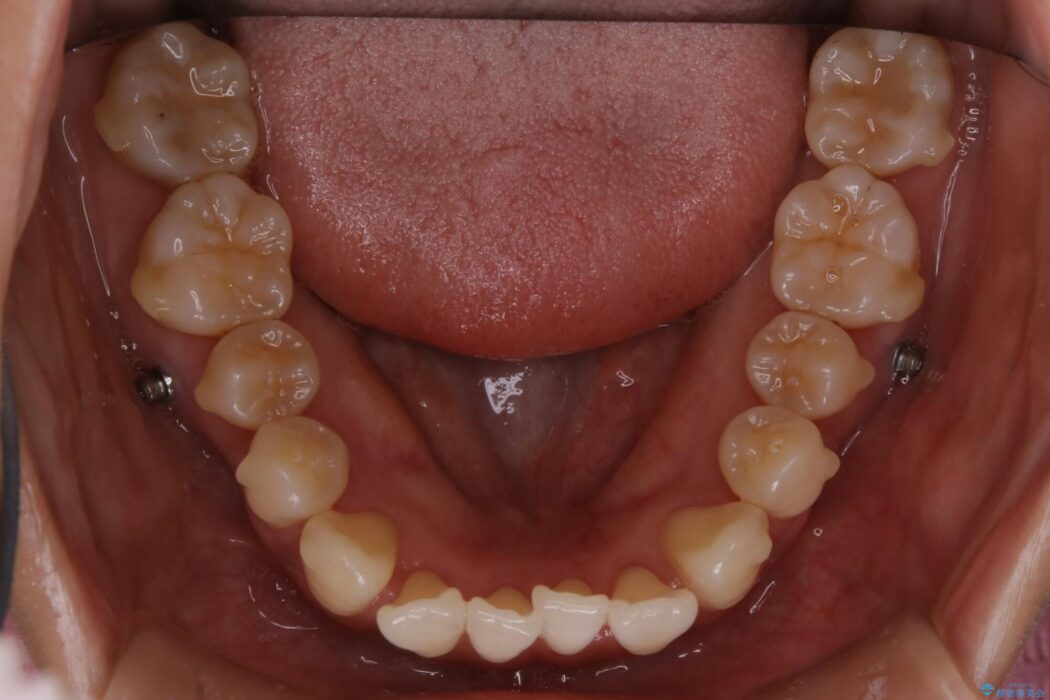

よってマイクロインプラントを用い、奥歯から順番に遠心移動させることによってスペースを確保することにしました。

歯を後方に移動させてスペースを確保する場合、マウスピースの装着時間に加えて装着時の適合度が良い状態に保たれているかが鍵となります。

歯は戻ろうとする力が強いためマウスピースの装着をしっかりしていただけなかった場合は、作り直しや治療の長期化につながってしまう可能性があります。